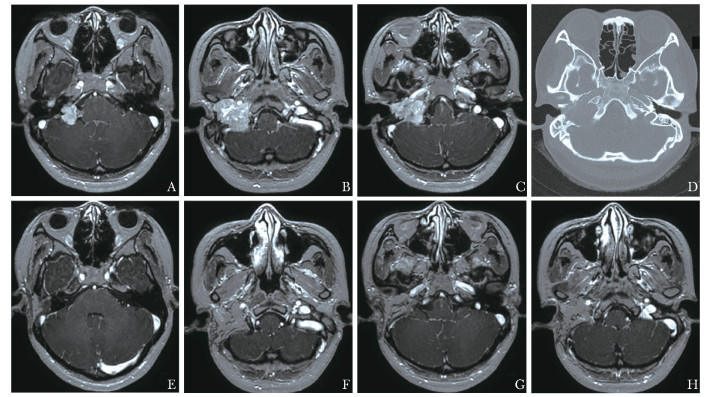

方法  回顾性分析2015年8月至2021年1月北京协和医院诊治的累及颈静脉孔区的侧颅底副神经节瘤患者临床资料。根据肿瘤与面神经的关系,术中对面神经进行不同方式的处理。对不同处理方式患者的术后面神经功能进行总结。

结果  共纳入30例累及颈静脉孔区的侧颅底副神经节瘤患者。Fisch分型为C1型3例,C2型6例,C2De1型2例,C2Di1型2例,C3De1型7例,C3Di1型5例,C3Di2型3例,C4De1型1例,C4Di1型1例。术前面神经功能House-Brackmann(HB)分级Ⅰ~Ⅱ级22例,Ⅲ级2例,Ⅳ级3例,Ⅴ级2例,Ⅵ级1例。经术后MRI检查证实,30例患者肿瘤均彻底切除。术后中位随访886 d,均未见复发。肿瘤未触及面神经15例,术中均行面神经前移,其中术后HB分级Ⅰ~Ⅱ级13例,Ⅲ级2例。肿瘤部分粘连面神经2例,术中均成功将面神经与肿瘤分离,其中术后HB分级Ⅰ~Ⅱ级1例,Ⅲ级1例。肿瘤包绕面神经13例,其中1例术中将面神经与肿瘤分离,术后HB分级Ⅲ级;余12例术中均未能将面神经与肿瘤分离,其中3例同期或分期行面神经重建,术后HB分级Ⅰ~Ⅱ级1例,Ⅲ级2例,余9例未行面神经重建,术后HB分级均为Ⅵ级。

Methods  We retrospectively analyzed the clinical data of patients with lateral skull base paraganglioma involving jugular foramen that were diagnosed and treated in Peking Union Medical College Hospital from August 2015 to January 2021. According to the relationship between the tumor and the facial nerve, the facial nerve was treated in different ways during the operation. The postoperative facial nerve function of patients with different treatments is summarized.

Results  A total of 30 patients with lateral skull base paraganglioma in the jugular foramen area were included. The Fisch classification of these patients was as followed: C1(n=3), C2(n=6), C2De1(n=2), C2Di1(n=2), C3De1(n=7), C3Di1(n=5), C3Di2(n=3), C4De1(n=1), C4Di1(n=1). Preoperative facial nerve function assessed by House-Brackmann (HB) grade: grade Ⅰ-Ⅱ (n=22), grade Ⅲ (n=2), grade Ⅳ (n=3), grade Ⅴ(n=2), grade Ⅵ(n=1). All tumors were completely resected, which was verified by post-operational MRI. No recurrence was observed during the medium follow-up of 886 days. All of the postoperative nerve function refers to the results of the last follow-up. Anterior facial nerve rerouting was performed in 15 cases whose tumor did not invade the facial nerve. The postoperative facial nerve function was HB grade Ⅰ-Ⅱ in 13 cases and HB grade Ⅲ in 2 cases. The tumors were adhesive to the facial nerve in 2 cases. The tumors and the facial nerve were successfully separated in both cases; one achieved HB grade Ⅰ-Ⅱ, while the other was HB grade Ⅰ-Ⅱ postoperatively. In 13 cases, the tumor wrapped the facial nerve. Among those patients, the tumor was separated from the facial nerve in 1 case, with the postoperative facial nerve function of HB grade Ⅲ. In the remaining 12 cases, the facial nerve was resected together with the tumor. Facial nerve reconstruction was performed in 3 cases in the same or the second surgery. The postoperative facial nerve function was HB gradeⅠ-Ⅱ in 1 case and HB grade Ⅲ in the other 2 cases. The postoperative facial nerve function in the remaining 9 cases that did not receive facial nerve reconstruction was HB grade Ⅵ.

Conclusions  In patients with lateral skull base paraganglioma, anterior facial nerve rerouting has a slight effect on the function of facial nerve, if the tumor does not invade the facial nerve. It is difficult to separate the tumor and the facial nerve, if the facial nerve is wrapped by the tumor, and the rate of postoperative facial nerve paralysis is higher in these cases.